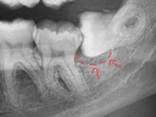

4 |

Quiste dentígero |

Lesión

unilocular, asintomática, radiolúcida, caracterizada por márgenes

escleróticos bien definidos y asociada con la corona de un diente sin

erupción.8 |

|